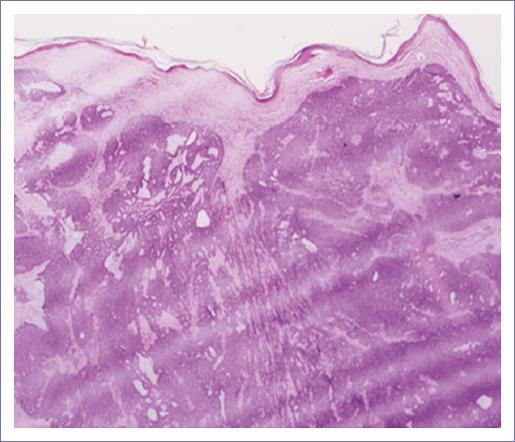

– Descripción microscópica. Los cortes histológicos examinados muestran la piel que presenta la epidermis sin alteraciones (Fig. 1); subyacente se observa tumor maligno de anexos cutáneos con patrón de crecimiento sólido, con proliferación de células de aspecto basaloide con núcleos vesiculosos. Pleomorfismo moderado y un índice mitósico de 4xCSF (40x) (Fig. 2). La neoplasia presenta formación de lúmenes intracitoplásmicos multifocales (Fig. 3). Los bordes del tumor son infiltrativos a nivel de dermis reticular (Fig. 4). No se identifica permeación vascular linfática. El lecho quirúrgico y bordes quirúrgicos no presentan lesión neoplásica.

Figura 1 Resección de neoformación de mejilla (magnificación 4x). Neoplasia sólida de epitelio de glándula sudorípara de bordes empujantes.